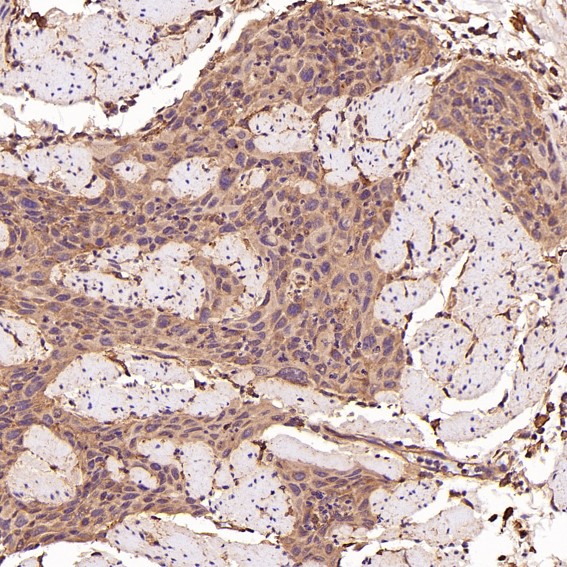

| IHC | IHC:1/100-1/200;IHF:1/50-1/200 | Human,Mouse,Rat |

Anti-Bim antibodies are vital tools for detecting Bim levels in research contexts, such as studying apoptosis mechanisms, cancer drug resistance, or neuronal survival. These antibodies (monoclonal/polyclonal) enable techniques like Western blot, immunohistochemistry, and flow cytometry. In cancer research, they help assess Bim’s role in chemotherapy response, as low Bim levels often predict poor outcomes. Additionally, Bim-targeting therapies, including BH3 mimetics, are explored to overcome apoptosis resistance. Reliable Bim antibodies are thus crucial for advancing both basic and translational biomedical research.